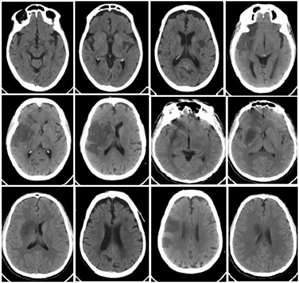

3. Data Acquisition

Figure 2. Corresponding SCT slices